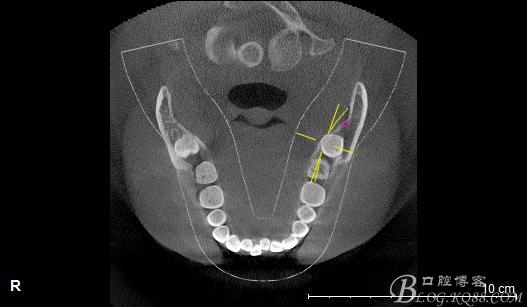

一、術(shù)前CBCT影像資料

口內(nèi):38未萌出。37遠中牙周袋10mm,CT:38牙冠倒置。牙齦紅腫,捫診可有少量血性滲出,無波動感。印象診斷:38冠周炎。處理:1.抗炎治療,改善張口度。2.炎癥消退后,拔除38.